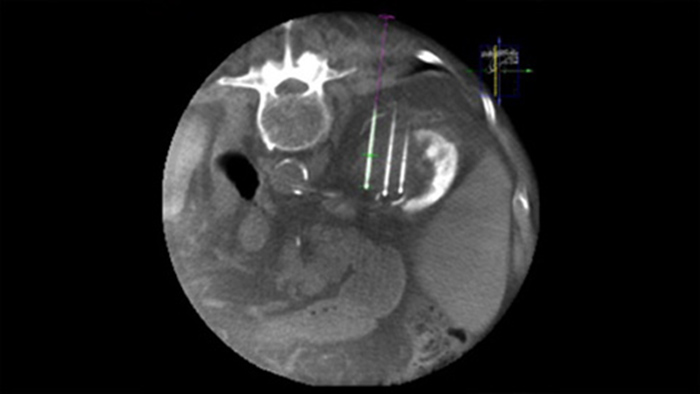

A ablação percutânea (radiofrequência, micro-ondas e crioablação) é um tratamento minimamente invasivo bem estabelecido contra tumores renais, hepáticos, pulmonares e ósseos. É fundamental definir os limites do tumor e decidir qual o número ideal de agulhas e a correspondente trajetória das agulhas para poder realizar um tratamento completo do tumor e não causar danos ao tecido circundante.

Navegar com precisão até a lesão em questão com baixa dose e sem reposicionamento da agulha aumenta a chance de sucesso e reduz o risco de complicações de suas biópsias ou ablações. A confirmação do desfecho do tratamento de ablação pode ser realizada com diagnósticos por imagem 3D enquanto o paciente ainda está na mesa.

Com a CBCT, você pode adquirir uma CBCT pós-ablação para demonstrar a extensão da cobertura do tumor e confirmar a completude do seu tratamento.